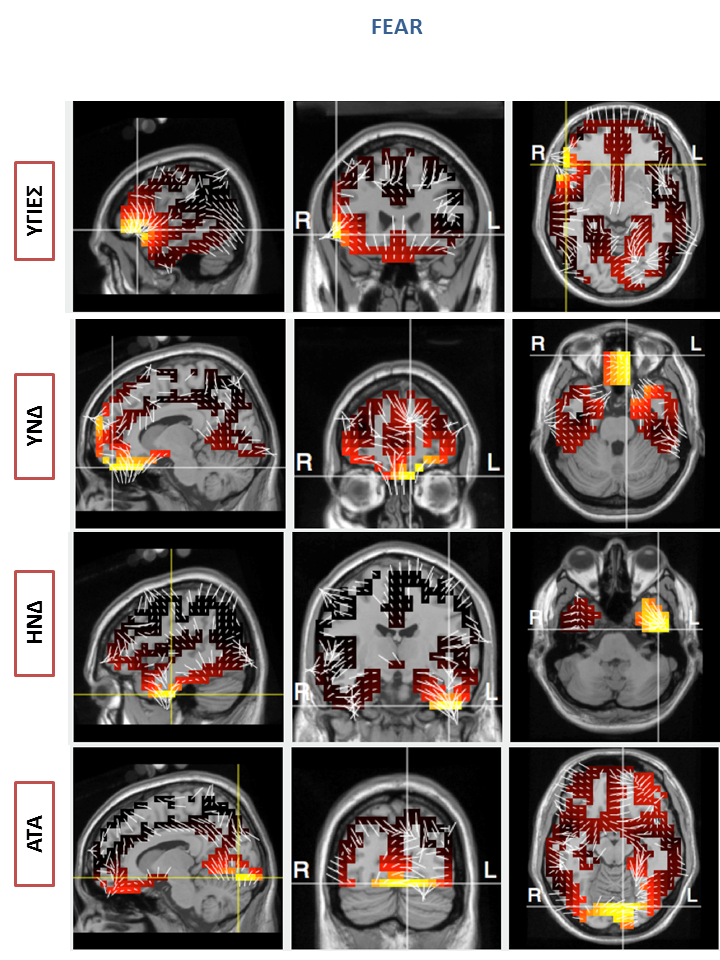

Ταυτόχρονα με την παρουσίαση των εικόνων γινόταν καταγραφή με τη χρήση του υψηλής ποιότητας-πυκνότητας ηλεκτροεγκεφαλογράφου EGI GES 300 με 256 ηλεκτρόδια, με στόχο την καταγραφή του σήματος του εγκεφάλου και τον εντοπισμό διαφορών ως προς τις περιοχές μέγιστης ενεργοποίησης μεταξύ των ομάδων. Τα αποτελέσματα της μελέτης έδειξαν στατιστικά σημαντικές διαφορές ως προς την απόκριση, αλλά και την ένταση της ενεργοποίησης συγκεκριμένων περιοχών μεταξύ των υγιών και των συμμετεχόντων με ΥΝΔ καθώς επίσης και τους συμμετέχοντες με ΗΝΔ κατά την διάρκεια της εξέτασης.

Ενώ όπως αναμενόταν, στην περίπτωση της ομάδας ΑΤΑ, οι ασθενείς παρουσίασαν την ελάχιστη ενεργοποίηση συγκεκριμένων περιοχών συγκριτικά με τις άλλες τρεις ομάδες. Σημαντικές διαφορές παρατηρήθηκαν επίσης στην τοπογραφική ανάλυση όπου επιβεβαίωσαν αυτή τη διαφορά, καθώς η βαρύτητα της νόσου αποδείχθηκε ότι επηρεάζει σημαντικά την ενεργοποίηση συγκεκριμένων περιοχών του εγκεφάλου που διαδραματίζουν σημαντικό ρόλο στην αντίληψη συναισθημάτων (Εικόνα 1). Συγκεκριμένα, παρατηρήθηκε μικρότερη ενεργοποίηση και δραστηριότητα στο μετωπιαίο και κροταφικό λοβό των συμμετεχόντων με ΥΝΔ σε σχέση με του υγιείς καθώς επίσης και μεταξύ των ασθενών με ΗΝΔ και ΑΤΑ (Εικόνα 2).

1) Εικόνα 1: Τοπογραφική ανάλυση, που επιβεβαιώνει τον εντοπισμό διαφορών σε περιοχές του εγκεφάλου των συμμετεχόντων με ΗΝΔ. Οι διαφορές αυτές διαδραματίζουν καθοριστικό ρόλο στην αντίληψη συναισθημάτων

Εικόνα 1